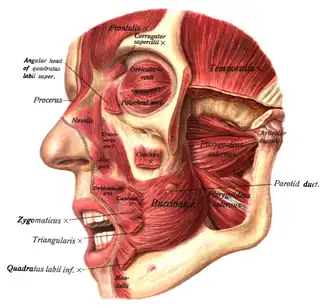

Additional images

-

-

-

-

-